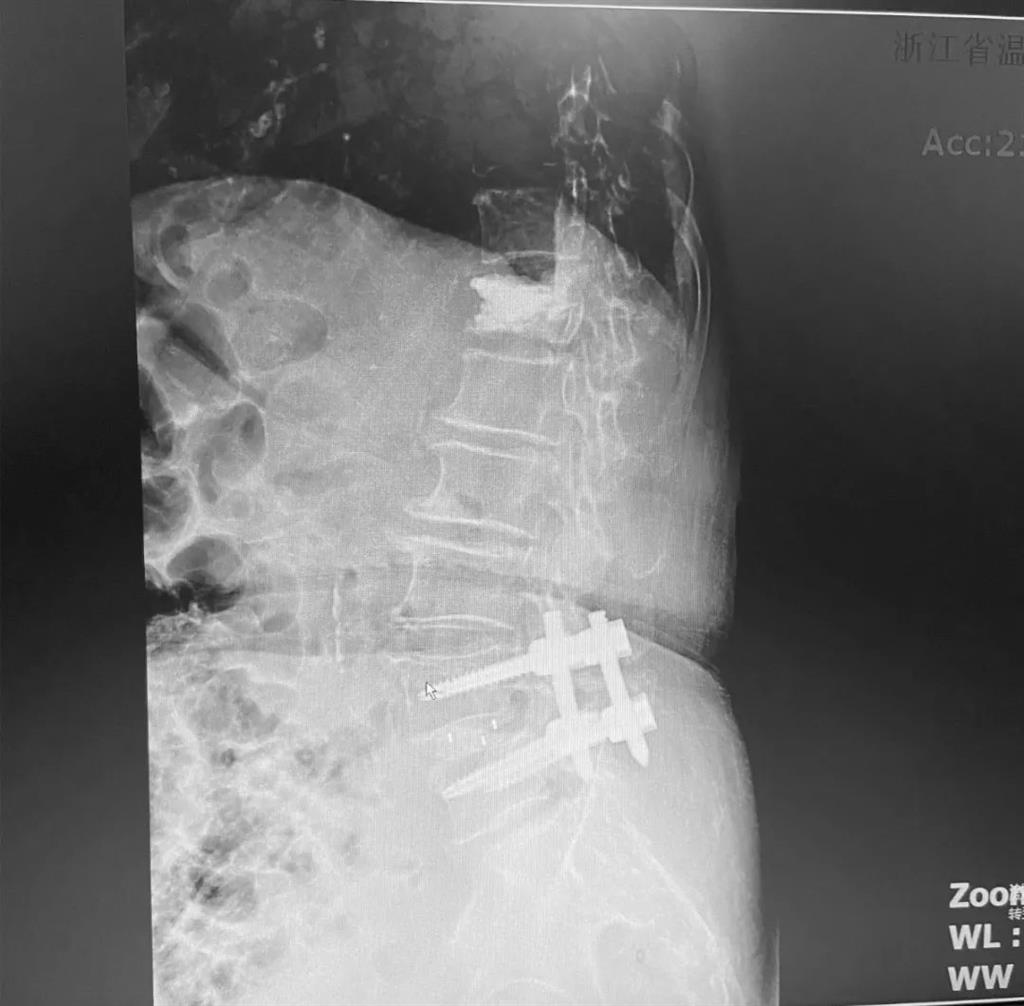

據(jù)了解,脊柱內(nèi)鏡下腰椎融合術(shù)只需要打幾個(gè)“鑰匙孔”即可完成。聽起來是不是很簡單?在脊柱內(nèi)鏡下,劉丹主任先后為患者進(jìn)行了椎管減壓、椎間盤摘除,再實(shí)施椎弓根螺釘放置、椎體植骨融合內(nèi)固定,一系列步驟有條不紊。

看似簡單的幾個(gè)步驟,但實(shí)際上很復(fù)雜,需要主刀醫(yī)生有豐富的手術(shù)經(jīng)驗(yàn)和細(xì)致耐心的操作。

而脊柱內(nèi)鏡下腰椎融合術(shù),作為目前國內(nèi)脊柱微創(chuàng)領(lǐng)域大力發(fā)展的新技術(shù),徹底改變了傳統(tǒng)開刀椎板切除椎間植骨融合內(nèi)固定的大創(chuàng)傷現(xiàn)狀,可以在較大程度上減少對脊柱后方穩(wěn)定結(jié)構(gòu)的破壞,創(chuàng)傷小,出血少,術(shù)后恢復(fù)快。

術(shù)中只需切開4個(gè)如“鑰匙孔”般大小的孔道